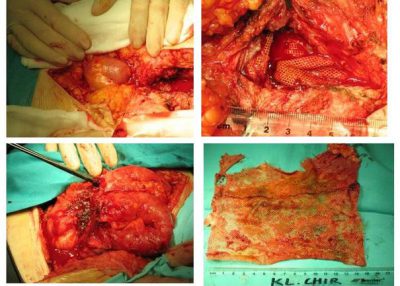

Przyczyną nieznośnego bólu może być złe umocowanie siatki – np. użycie nie wchłaniających się zszywek. Obok zdjęcia z usuwania siatki z mocowanej metalowymi zszywkami, które (co oczywiste) bolały chorego. Ból, uczucie stałej przeszkody był nie do wytrzymania. W czasie operacji okazało się, że metalowych zszywek jest bardzo dużo, były ostre, kłuły. Sama siatka była sztywna i niedopasowana do ciała młodego człowieka. Jedynym rozwiązaniem było usunięcie siatki z zszywkami.

Usuwanie siatki to zwykle rozległa operacja i ciało jest okaleczone. Po usunięciu siatki może powstać nawrót przepukliny. Nie wykluczone, że chorego czeka kolejna operacja; na siatkę już się nie zdecyduje.

Na zdjęciach stwardniałe, obkurczone siatki usunięte w czasie ponownych operacji.